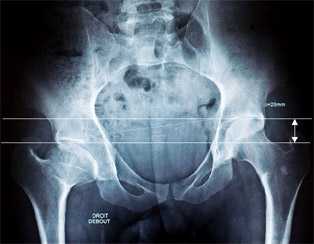

Une Jambe plus courte que l’autre se confirme en prenant une radiographie du bassin de face. On mesure ainsi le déficit en mm, en comparant la différence de hauteur entre les sommets des têtes fémorales droite et gauche.

Un grand nombre de personnes ignorent qu’elles ont une ILMI. En effet, soit le déficit (la différence de hauteur entre les sommets des têtes fémorales droite et gauche) est faible, et l’on peut très bien vivre toute sa vie sans ne jamais ressentir aucune gêne, soit le déficit est plus marqué et les lombalgies ou les douleurs articulaires dans la hanche peuvent se déclenchées beaucoup plus tard.

Depuis 1988, date à laquelle nous avons commencé à exercer en cabinet auprès de nos patients et à la réalisation de leurs semelles orthopédiques sur mesure, nous avons toujours entendu la même préconisation pour corriger une ILMI, « compenser de 50% le déficit de la bascule du bassin », c’est-à-dire, compenser la jambe plus courte par la moitié de la hauteur constatée à la radiographie du bassin entre le sommet des 2 têtes fémorales.